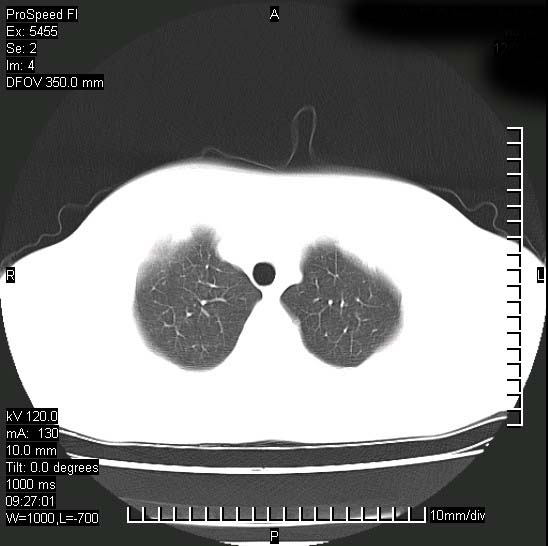

以下是引用zjzjr在2008-12-3 20:50:00的发言:[br]考虑泛细支气管肺炎,建议进一步检查除外肺出血性疾病如含铁血黄素沉着症、肺肾综合征等。

以下是引用zjzjr在2008-12-3 20:50:00的发言:[br]考虑泛细支气管肺炎,建议进一步检查除外肺出血性疾病如含铁血黄素沉着症、肺肾综合征等。

以下是引用光线在2008-12-3 20:19:00的发言:[br]双肺间质性改变。